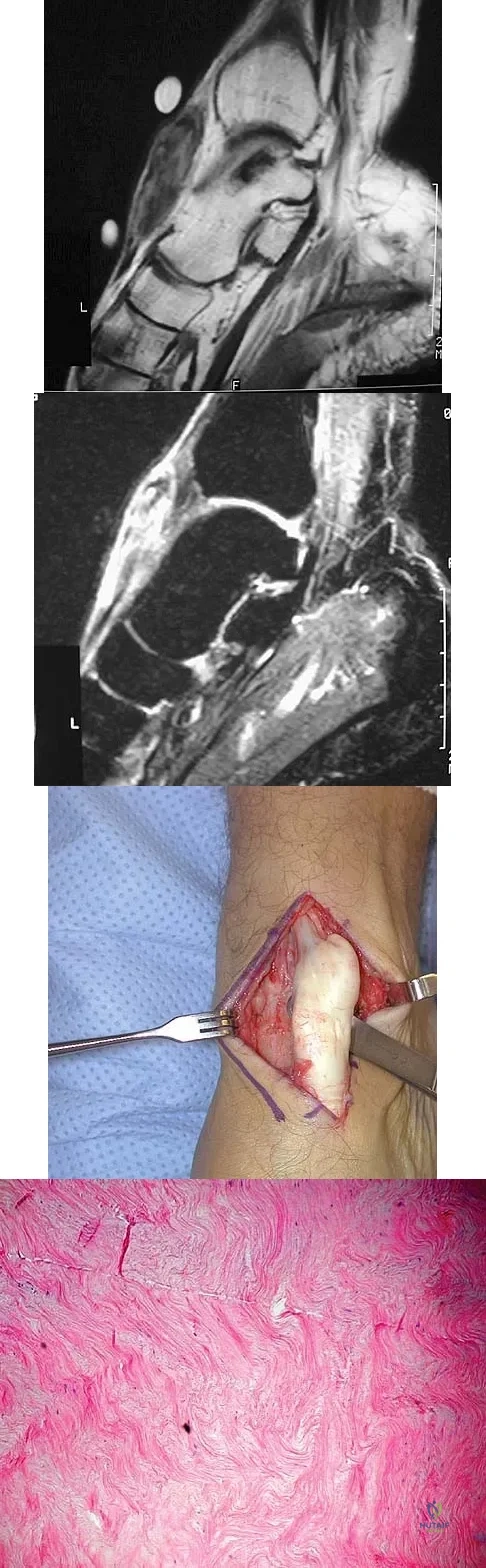

A 40-year-old man has a palpable mass over the dorsum of the ankle. He reports no history of direct trauma but notes that he sustained a laceration to the middle of his leg 6 weeks ago. Examination reveals a 4-cm x 1-cm mass. T1- and T2-weighted MRI scans are shown in Figures 12a and 12b. An intraoperative photograph and biopsy specimen are shown in Figures 12c and 12d. What is the most likely diagnosis?

A 16-year-old girl has had painless swelling in her posterior left arm for the past 4 months. A radiograph, MRI scans, and an incisional biopsy specimen are shown in Figures 43a through 43d. What is the cytogenetic translocation most commonly associated with this tumor?